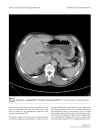

Experience with adjuvant chemotherapy for pseudomyxoma peritonei secondary to mucinous adenocarcinoma of the appendix with oxaliplatin/fluorouracil/leucovorin (FOLFOX4